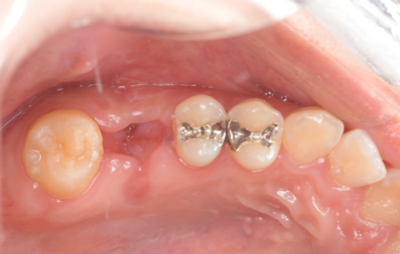

移植3ヶ月後の口腔内写真

移植3ヶ月後。

歯根周囲に透過像を認めるが動揺などはなく、歯周ポケットも形成されていなかった。

移植12ヶ月後の口腔内写真

移植12ヶ月後。セラミッククラウンで歯冠を修復した。